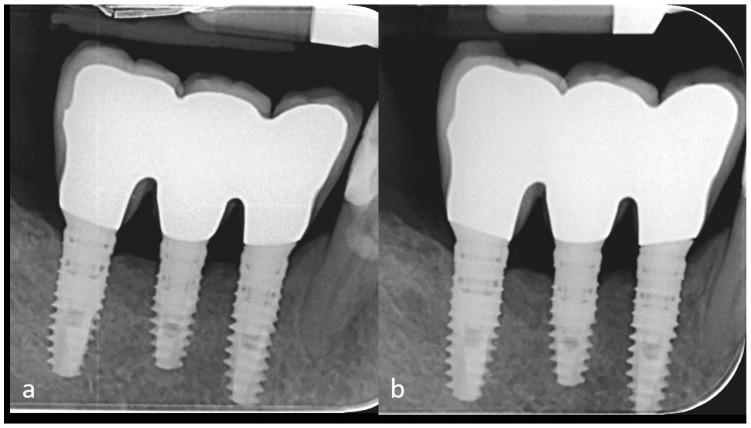

One of the most often used bone augmentation techniques is the guided bone regeneration procedure. The authors report the case of a 75-year-old man with an atrophic right posterior mandible who underwent bone augmentation through guided bone regeneration with a preshaped titanium mesh adapted on a stereolithographic model of the patient's jaw. The graft volume was simulated with a light-curing resin. The actual site was grafted with a mixture of autogenous and equine-derived bone. Five months later, the mesh was retrieved, three cylindrical implants were positioned, and a bone biopsy was collected for histomorphometric analysis. A provisional prosthesis was delivered three and a half months later. Definitive rehabilitation was accomplished after one additional month. The graft allowed for effective bone formation (newly formed bone, residual biomaterial, and medullar spaces were, respectively, 39%, 10%, and 51% of the core volume). The patient has functioned successfully throughout six and a half years of follow-up. Using the preshaped titanium mesh in association with the enzyme-treated equine bone substitute provided effective bone regeneration.

最常用的骨增量技术之一是引导骨再生术。作者报告了一例75岁男性患者,其右侧下颌骨萎缩,通过引导骨再生术进行骨增量,使用了根据患者颌骨的立体光刻模型定制的预成型钛网。用光固化树脂模拟移植骨体积。实际部位植入了自体骨和马源骨的混合物。五个月后,取出钛网,植入3枚圆柱形种植体,并采集骨活检样本进行组织形态计量学分析。三个半月后安装临时义齿。再过一个月完成最终修复。移植骨实现了有效的骨形成(新形成的骨、残余生物材料和骨髓腔分别占核心体积的39%、10%和51%)。在六年半的随访期间,患者功能良好。使用预成型钛网联合酶处理的马骨替代物可实现有效的骨再生。